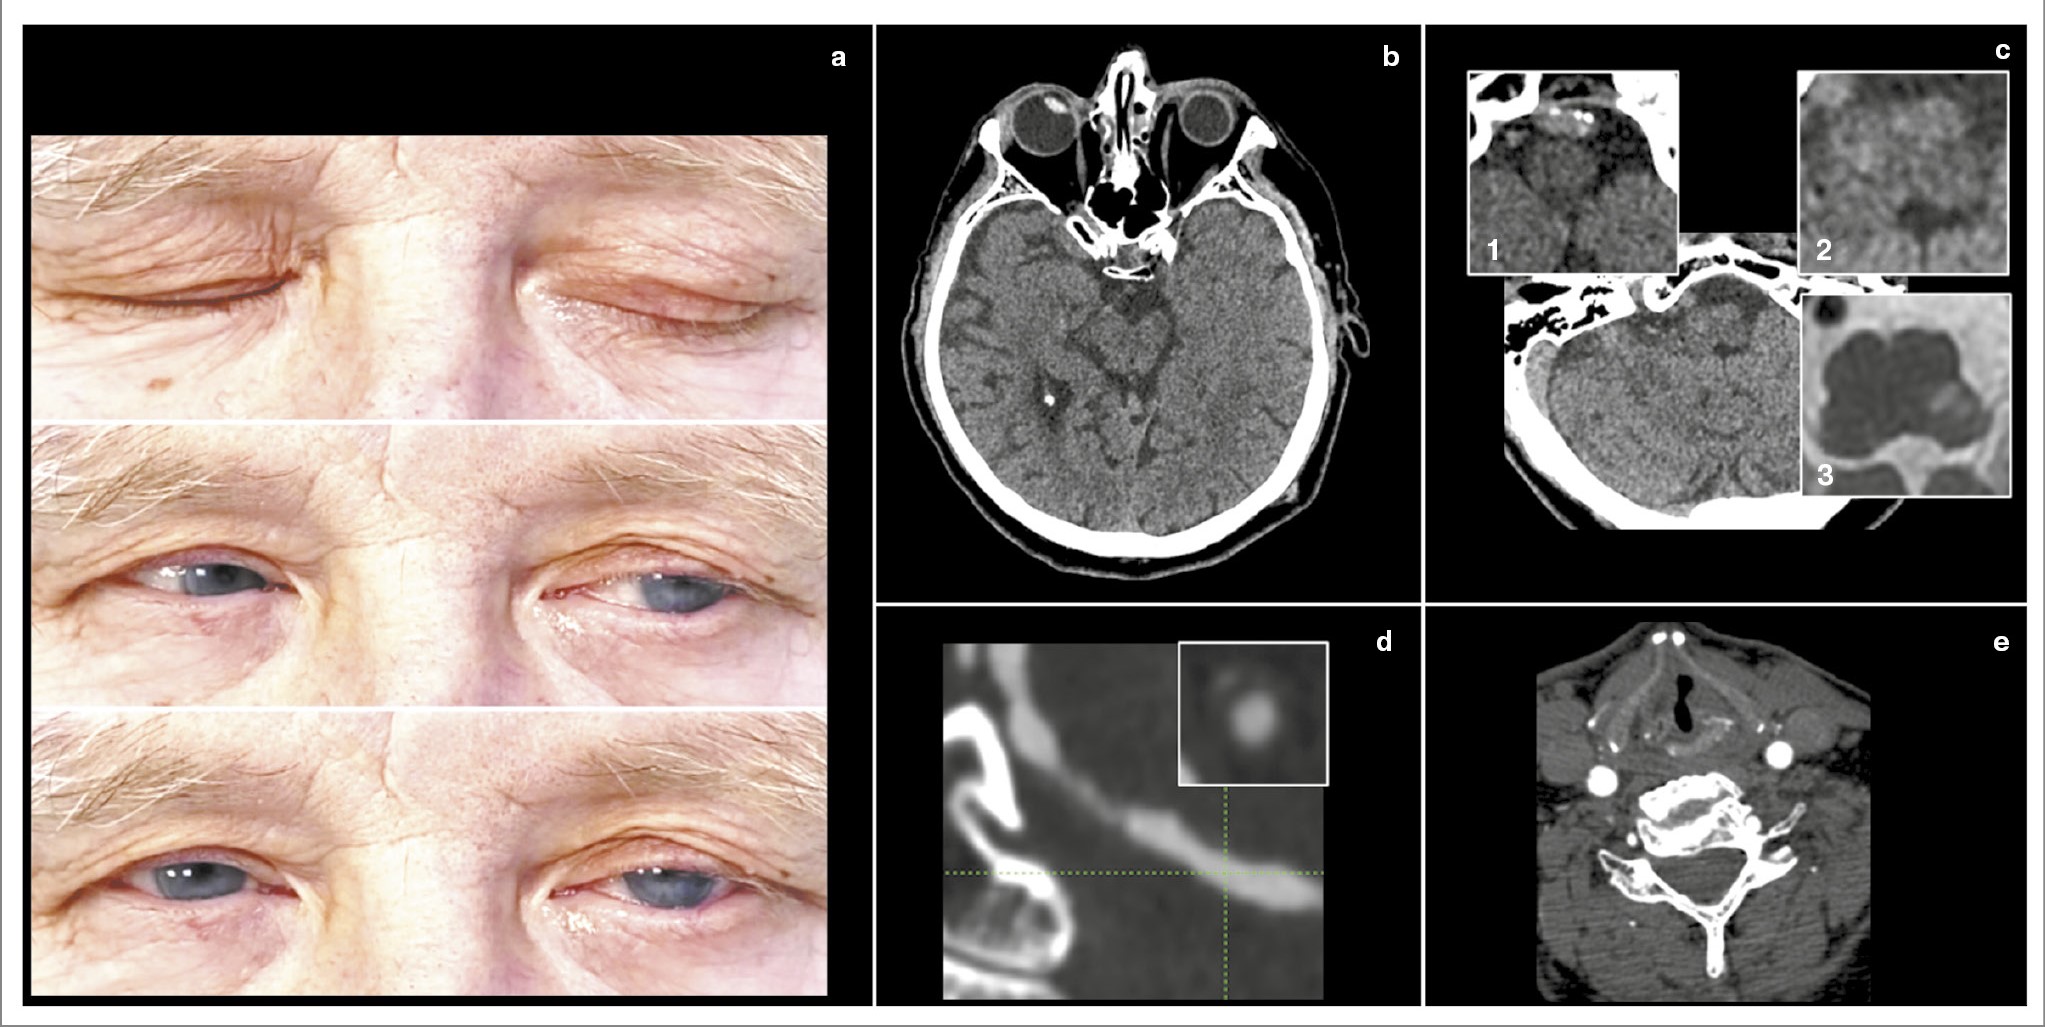

Рис. 5. Клинический пример синдрома Опальского. Пациент 51 года. Длительное время страдает артериальной гипертензией и сахарным диабетом 2-го типа, в 2018 г. перенес инфаркт миокарда. 2 декабря 2022 г. вечером почувствовал головокружение, шаткость при ходьбе. На следующий день появилась слабость в левой ноге. Поступил через сутки после возникновения первых симптомов. В неврологическом статусе при поступлении – интенсивный горизонтальный нистагм, направленный вправо, положительный OLD-тест слева, синдром Горнера слева (a, верхнее изображение), легкий левосторонний гемипарез (a, нижнее изображение), дизартрия и икота. Выполнена КТ головного мозга, визуализированы кальцификаты в проекции IV сегмента левой позвоночной артерии, а также выраженная содружественная девиация глаз влево (b). При проведении КТА выявлен выраженный стеноз IV сегмента правой позвоночной артерии (c), а также медиальное смещение левой голосовой связки, свидетельствующее о ее парезе (d). МРТ, выполненная на следующий день, позволила визуализировать инфаркт дорсолатеральных отделов продолговатого мозга слева, распространяющийся ниже перекреста пирамид (e). При введении контраста обнаружено его интенсивное концентрическое накопление стенкой IV сегмента левой позвоночной артерии, свидетельствующее о нестабильной субстенотической атероме (f).